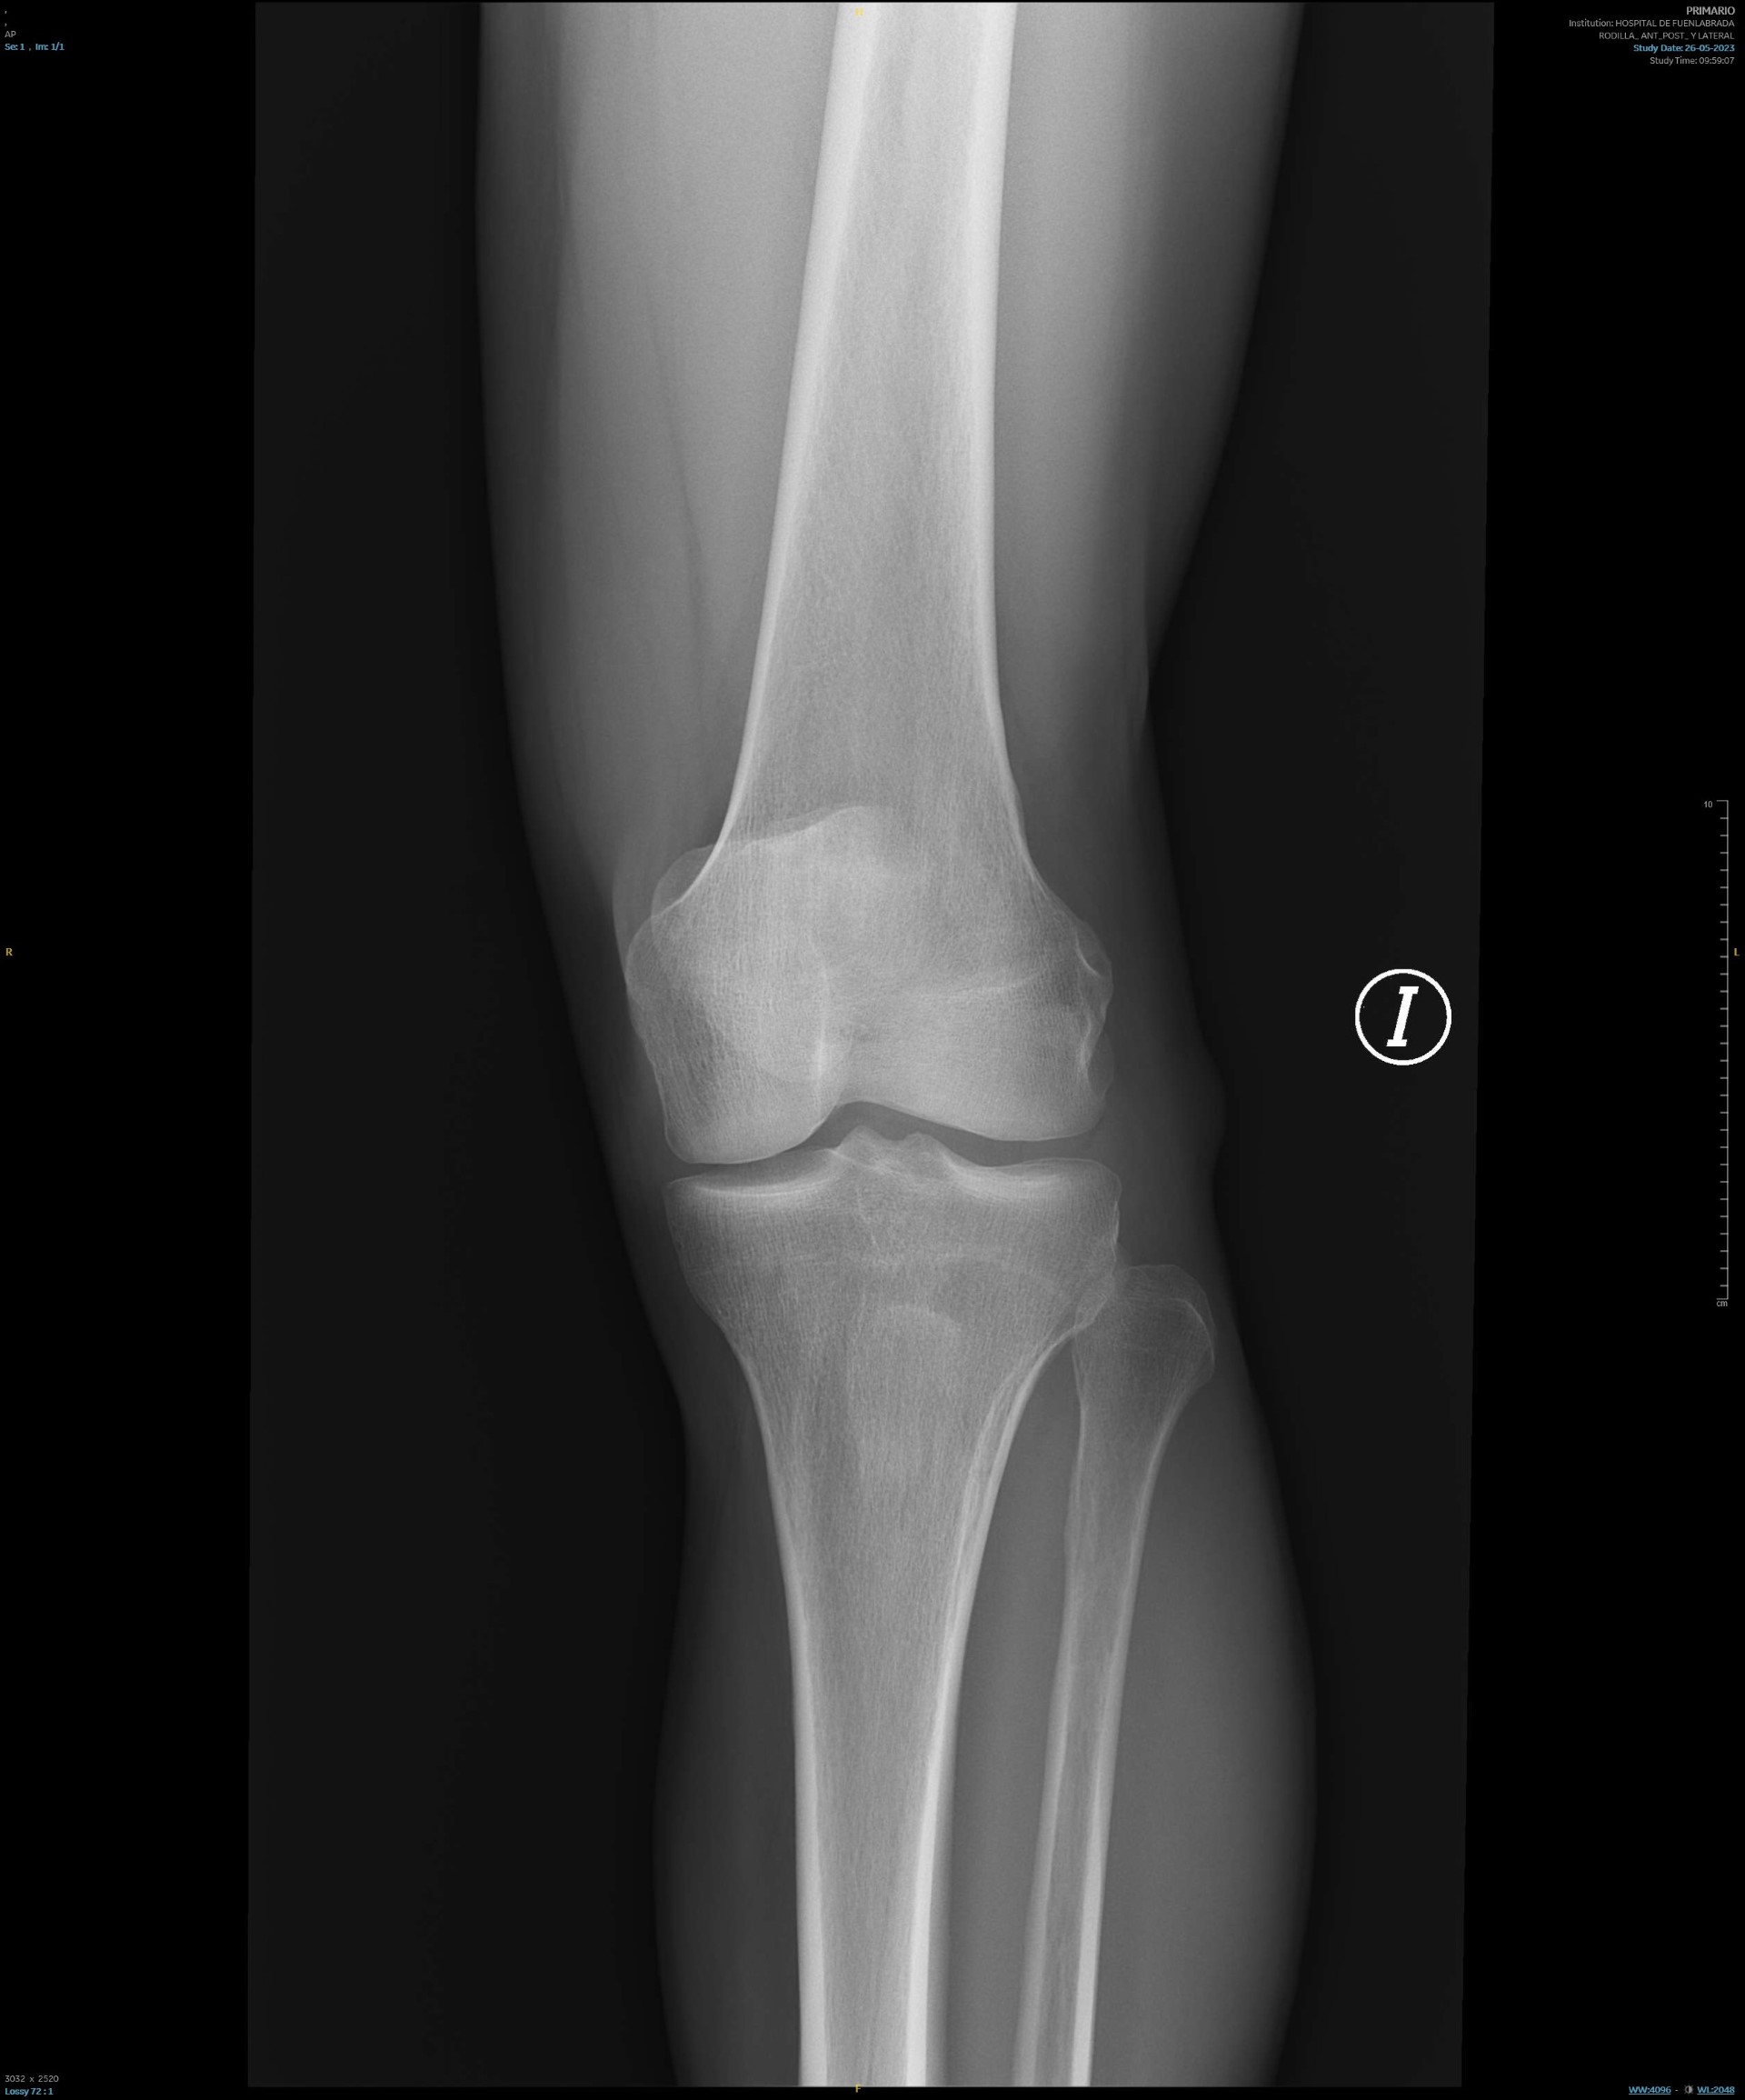

Rx de rodilla: sin alteraciones.